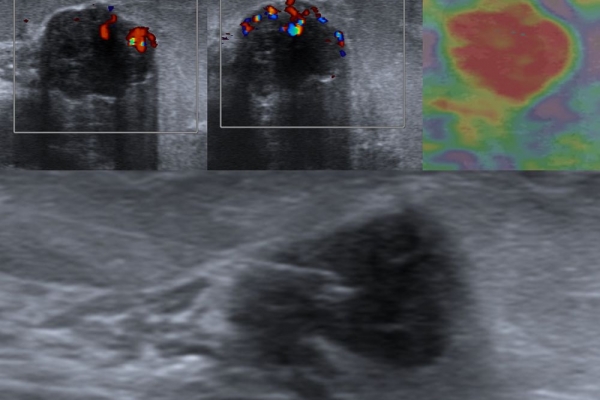

- Παρακέντηση με λεπτή βελόνη - FNA (fine needle aspiration). Είναι η απλούστερη επεμβατική μέθοδος βιοψίας μαστού. Υπό συνεχή υπερηχογραφική καθοδήγηση εισάγεται μια λεπτή βελόνη εντός του ύποπτου ευρήματος και αναρροφάται το περιεχόμενο, το οποίο μπορεί να δοθεί για κυτταρολογικό έλεγχο και/ή καλλιέργεια σε υποψία φλεγμονής.Είναι γρήγορη και είναι πολύ καλά ανεκτή χωρίς επιπλοκές. Η μέθοδος εφαρμόζεται:

- σε υπερηχογραφικά ύποπτους λεμφαδένες